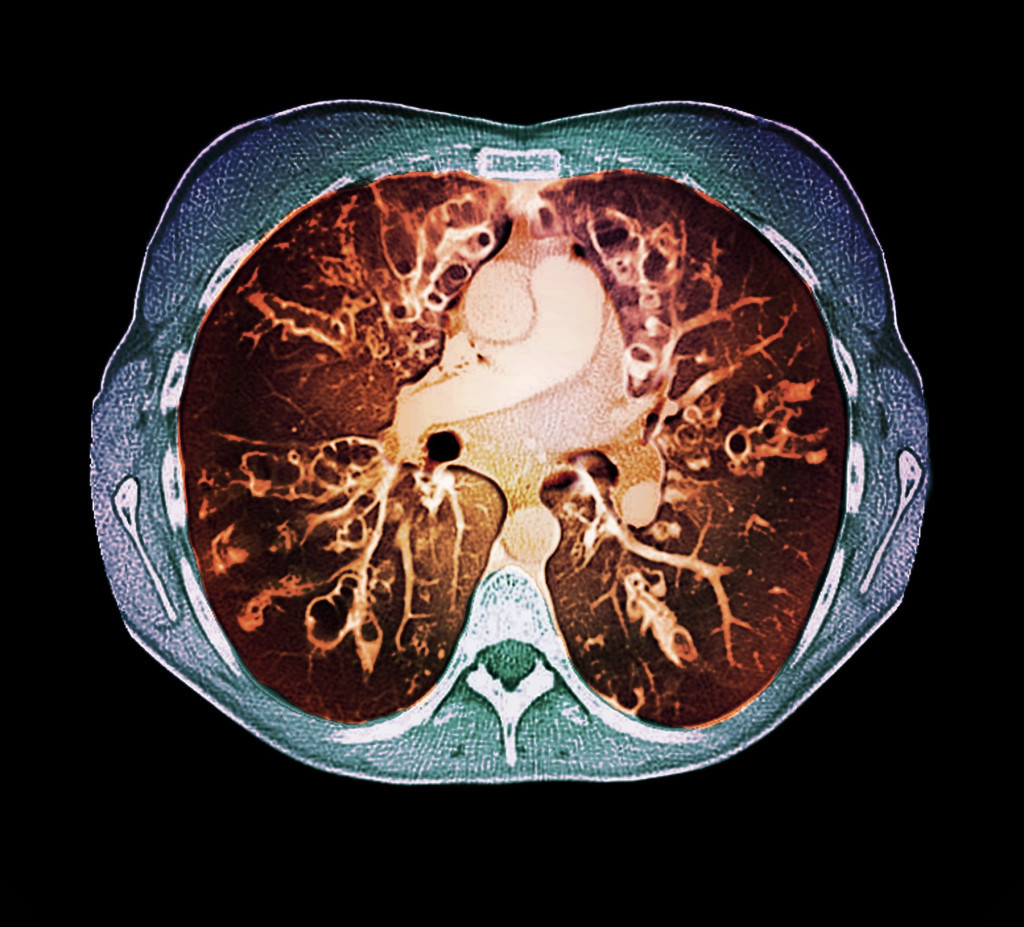

U Srbiji trenutno ima oko 400 pacijenata obolelih od cistične fibroze, a, kako je istaknuto na konferenciji posvećenoj toj retkoj i naslednoj bolesti danas u Beogradu, u avgustu bi trebalo da bude dostupan novi lek koji će, samo jednom tabletom dnevno, svesti simptome bolesti na minimum.

Pedijatar pulmolog Klinike za pedijatriju Univerzitetskog kliničkog centra u Kragujevcu Anđelka Stojković istakla je da je u poslednjih petnaestak godina u Srbiji umnogome unapređen sistem lečenja i dijagnostike kada je reč o cističnoj fibrozi.

- Očekujemo vrlo brzo, u avgustu ove godine, da stigne lek, gde ćemo jednom tabletom, umesto dve dnevno, učiniti modulaciju disajnih organa i svih epitelnih ćelija i na taj način mnogo bolje rešiti problem cistične fibroze, nego što je to ikada bilo do sada. Smanjićemo tom jednom tabletom upotrebu ostalih lekova, inhalacionih i onih lekova koje su ti pacijenti morali da uzmu na dnevnoj bazi - najavila je Stojković.

Ona je dodala da zbog kompleksnosti bolesti pacijenti sa cističnom fibrozom uzimaju i do 20 tableta dnevno kako bi nadomestili određene funkcije vitalnih organa.

U poslednje četiri godine u Srbiji je dostupan skrininig za rano otkrivanje bolesti, a Stojković je izrazila nadu da će ubrzo biti dostupan i prenatalni skrining kojim se može utvrditi postoji li mogućnost da beba kada se rodi ima cističnu fibrozu.